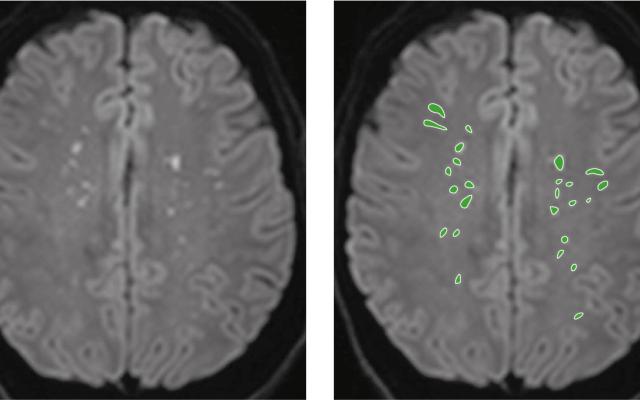

Het vetemboliesyndroom bij fracturen ontstaat waarschijnlijk door circulerende vetdeeltjes die afkomstig zijn uit het beenmerg en die emboliseren in de longen en de hersenen. Dit heeft respiratoire insufficiëntie en neurologische uitvalsverschijnselen tot gevolg. Wij beschrijven de diagnostische werkstroom bij twee patiënten die na een traumatische femurfractuur het vetemboliesyndroom ontwikkelden.